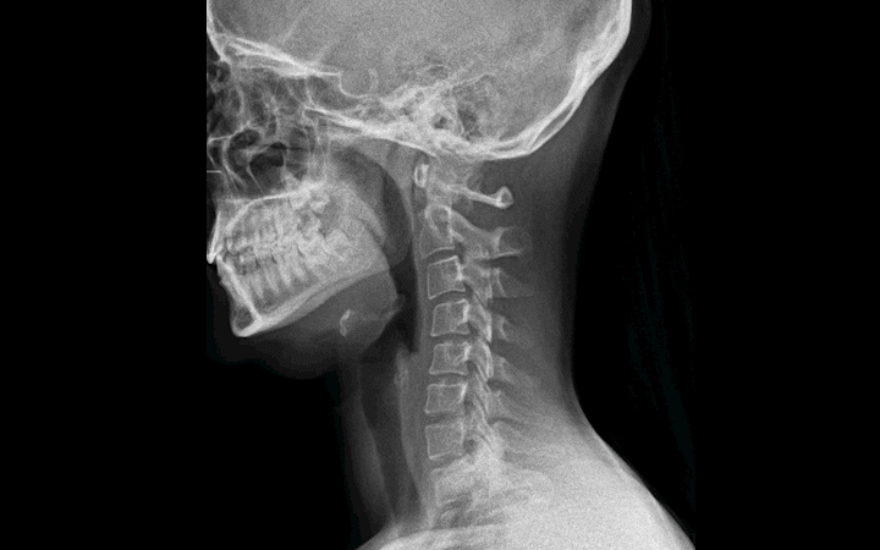

La radiología digital dinámica permite ver la anatomía del paciente en movimiento

La radiología digital dinámica (Dynamic Digital Radiography -DDR, por sus siglas en inglés) es una innovadora tecnología de rayos X que permite obtener series de imágenes digitales en la que se aprecia la anatomía en movimiento. "El equipo, emite 15 pulsos por segundo durante un tiempo de exposición de 15 segundos, lo que ofrece una imagen dinámica de la anatomía del paciente de forma muy rápida", explica el Dr. Vicente Martínez de Vega

, jefe del Servicio de Diagnóstico por la Imagen del Hospital Universitario Quirónsalud Madrid, que dispone del primer equipo portátil en Europa de estas características. Este equipamiento de la empresa Konica Minolta ofrece a los radiólogos la posibilidad de capturar y analizar el movimiento fisiológico de una estructura corporal con una dosis muy inferior a un estudio por fluoroscopia.

"La radiología digital dinámica tiene utilidad en los estudios ortopédicos en los que se aprecia una imagen radiográfica del movimiento de las articulaciones como la muñeca, el hombro o la rodilla. También tiene gran utilidad para estudiar la columna en flexión y extensión. Nos ofrece una visión muy completa del movimiento de la articulación", explica el Dr. Martínez de Vega, que también cree que esta nueva tecnología tiene otro punto fuerte en los estudios de función pulmonar: "Puede tomar imágenes de dos o tres respiraciones completas del paciente y mostrarnos una imagen en movimiento en el que se visualiza con claridad cómo se llenan y vacían los pulmones y el movimiento del diafragma. Se aprecia si existen adherencias pleurales o si hay zonas que no ventilan correctamente. A la información visual del cineloop (imágenes en secuencia), se pueden añadir mapas de ventilación y del movimiento realizados gracias a softwares avanzados específicos de la estación de trabajo, que analizan las diferentes densidades del pulmón y ofrecen al radiólogo datos cuantificables de función pulmonar". Según el Dr. Martínez de Vega, esta información es muy útil en las Unidades de Cuidados Intensivos en los que ayudará a valorar más adecuadamente la evolución de los pacientes desde el punto de vista cardiopulmonar. Otra gran ventaja de este equipo es que es portátil, lo que permite realizar los estudios a pie de cama de los pacientes sin necesidad de desplazarlos.

"La radiación que recibe un paciente que se somete a una radiografía digital dinámica es similar a una placa postero-anterior y lateral de rayos X convencional, pero aporta mucha más información", detalla el Dr. Martínez de Vega, que afirma que la radiología digital dinámica ofrece una información nueva que no habíamos visto hasta ahora: "Hemos pasado de obtener información morfológica a información funcional y cuantificada".